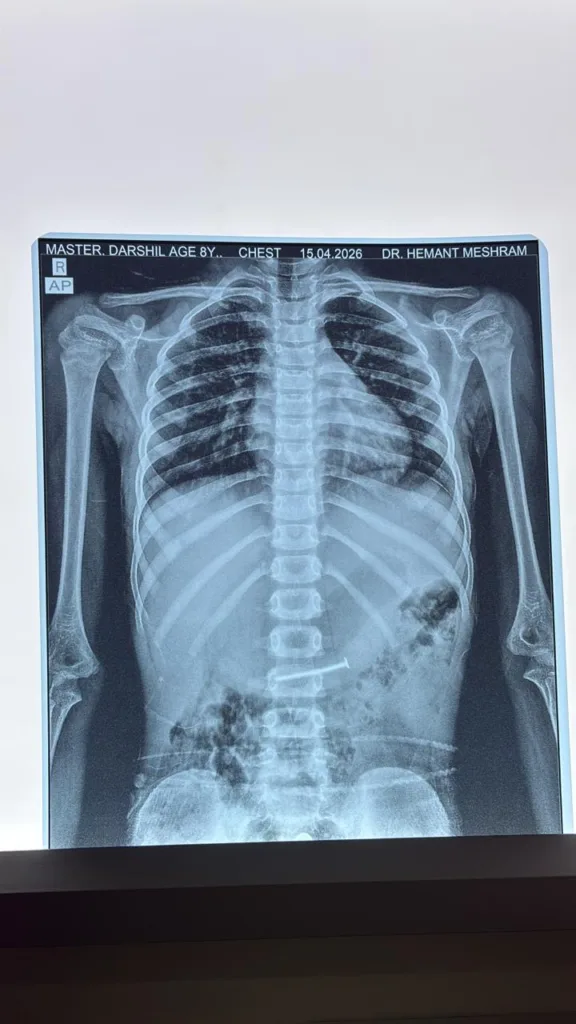

सतपुड़ा एक्सप्रेस।छिंदवाड़ा स्थित क्लैरिस हॉस्पिटल में एक जटिल और चुनौतीपूर्ण मेडिकल केस का सफलतापूर्वक उपचार किया गया, जिसने चिकित्सा क्षेत्र में एक नई मिसाल पेश की है।यह मामला उमरेठ निवासी 8 वर्षीय दर्शील सोनी का है, जिसने गलती से लोहे की नुकीली कील निगल ली थी।

परिजन तुरंत बच्चे को अस्पताल लेकर पहुंचे, जहां विशेषज्ञ चिकित्सक डॉ. मनन गोगिया ने स्थिति की गंभीरता को देखते हुए तत्काल जांच की।जांच में पता चला कि कील बच्चे के पेट में खतरनाक स्थिति में फंसी हुई थी, जिससे आंतरिक चोट का गंभीर खतरा बना हुआ था।

ऐसे मामलों में सामान्यतः ओपन सर्जरी की आवश्यकता होती है, लेकिन यहां आधुनिक तकनीक का सहारा लिया गया।डॉक्टर ने दूरबीन पद्धति (एंडोस्कोपी) का उपयोग करते हुए बेहद सावधानी और कुशलता के साथ कील को सफलतापूर्वक बाहर निकाल लिया। यह प्रक्रिया अत्यंत जटिल थी, क्योंकि थोड़ी सी भी चूक से गंभीर नुकसान हो सकता था।।

सफल प्रक्रिया के बाद बच्चा पूरी तरह स्वस्थ हो गया और उसे अस्पताल से छुट्टी दे दी गई।यह उपलब्धि अस्पताल की उन्नत चिकित्सा सुविधाओं और चिकित्सकों की विशेषज्ञता का प्रमाण है।